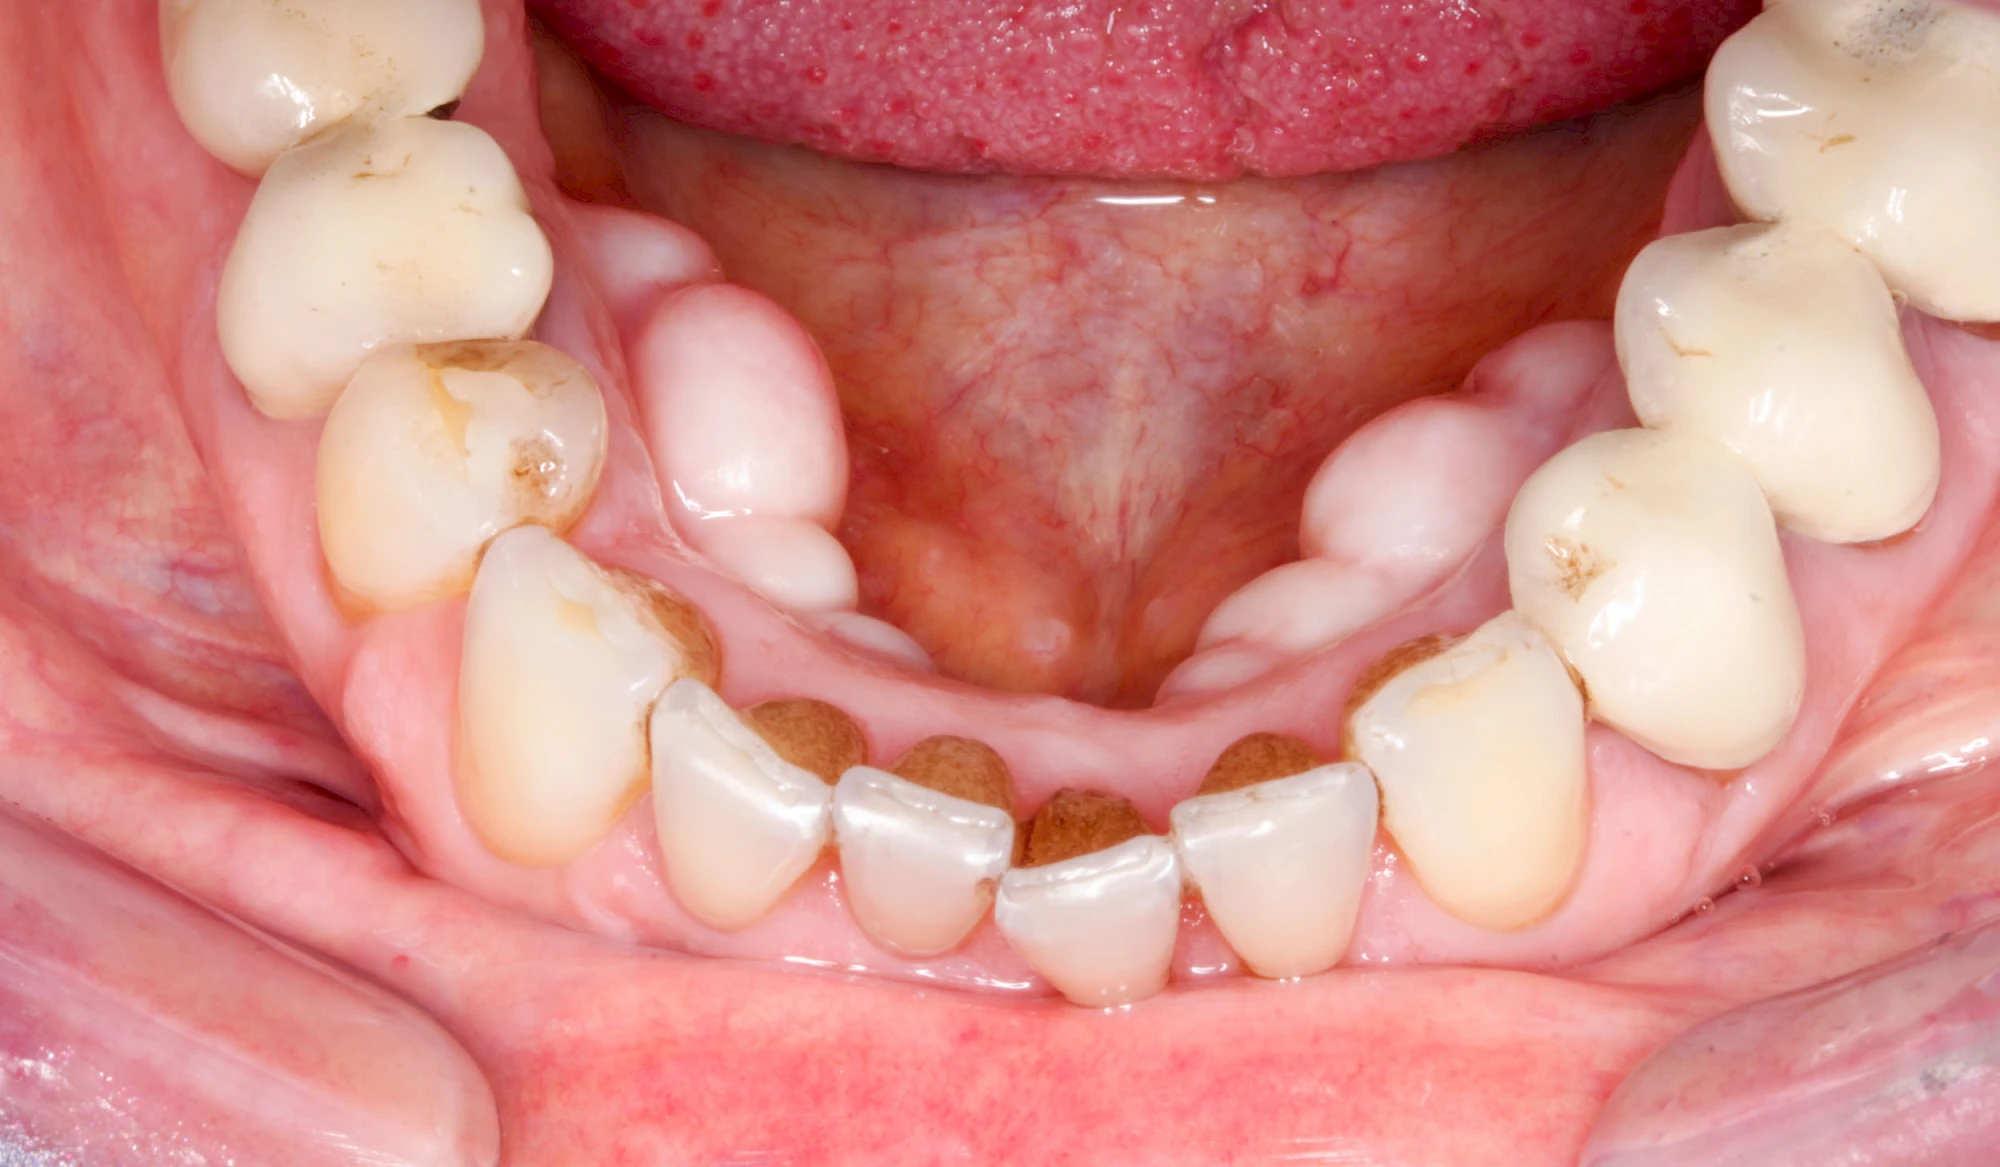

Lippen-Kiefer-Gaumenspalte

Lippen-Kiefer-Gaumenspalten (LKG-Spalte) sind angeborene Fehlbildungen im Mund-Kiefer-Gesichtsbereich. Die Gewebestrukturen im Bereich des Oberkiefers sind im Zuge der Entwicklungen bis zur Geburt nicht zusammengewachsen. Diese Fehlbildung zählt zu den häufigsten Fehlbildungen des Menschen, von 500 Neugeborenen ist eines betroffen. Die Fehlbildungen können sich auf Lippe, Gaumen und Kiefer allein beschränken, treten häufig aber kombiniert und in seltenen Fällen sogar beidseits auf.

Heute werden in Deutschland Menschen mit Lippen-Kiefer-Gaumenspalten bereits ab Geburt von Experten verschiedener Fachrichtungen (Mund-Kiefer-Gesichtschirurgen, Kieferorthopäden, Logopäden) betreut, damit entsprechende Korrekturen schon frühzeitig erfolgen können. Gerade jedoch bei älteren Menschen ist dies nicht immer geschehen. Diese Menschen tragen häufig technisch aufwendige Zahnprothesen.